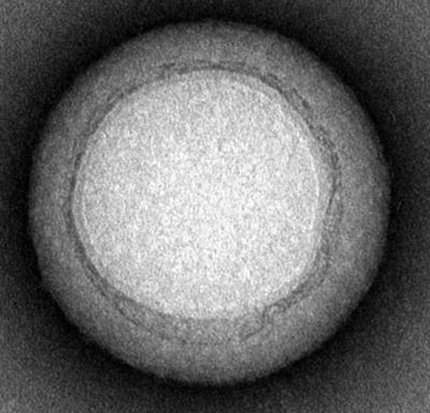

Los nanotecnólogos resolvieron este problema creando para las nanopartículas una cobertura compuesta por una membrana celular de eritrocitos. La cobertura protege a las nanopartículas de los leucocitos y mejora su capacidad de absorber las moléculas del veneno que intentan destruir los eritrocitos.

La esponja fue probada en ratones a los que se les inyectó el estafilococo áureo. Las nanopartículas permanecieron más de 40 horas en la sangre de los ratones y absorbieron la mayor parte de las toxinas. Después de desintegrarse las partículas, la nanocobertura fue transferida al hígado, donde las toxinas fueron neutralizadas. Actualmente científicos planean aplicar la nueva técnica en pruebas clínicas.